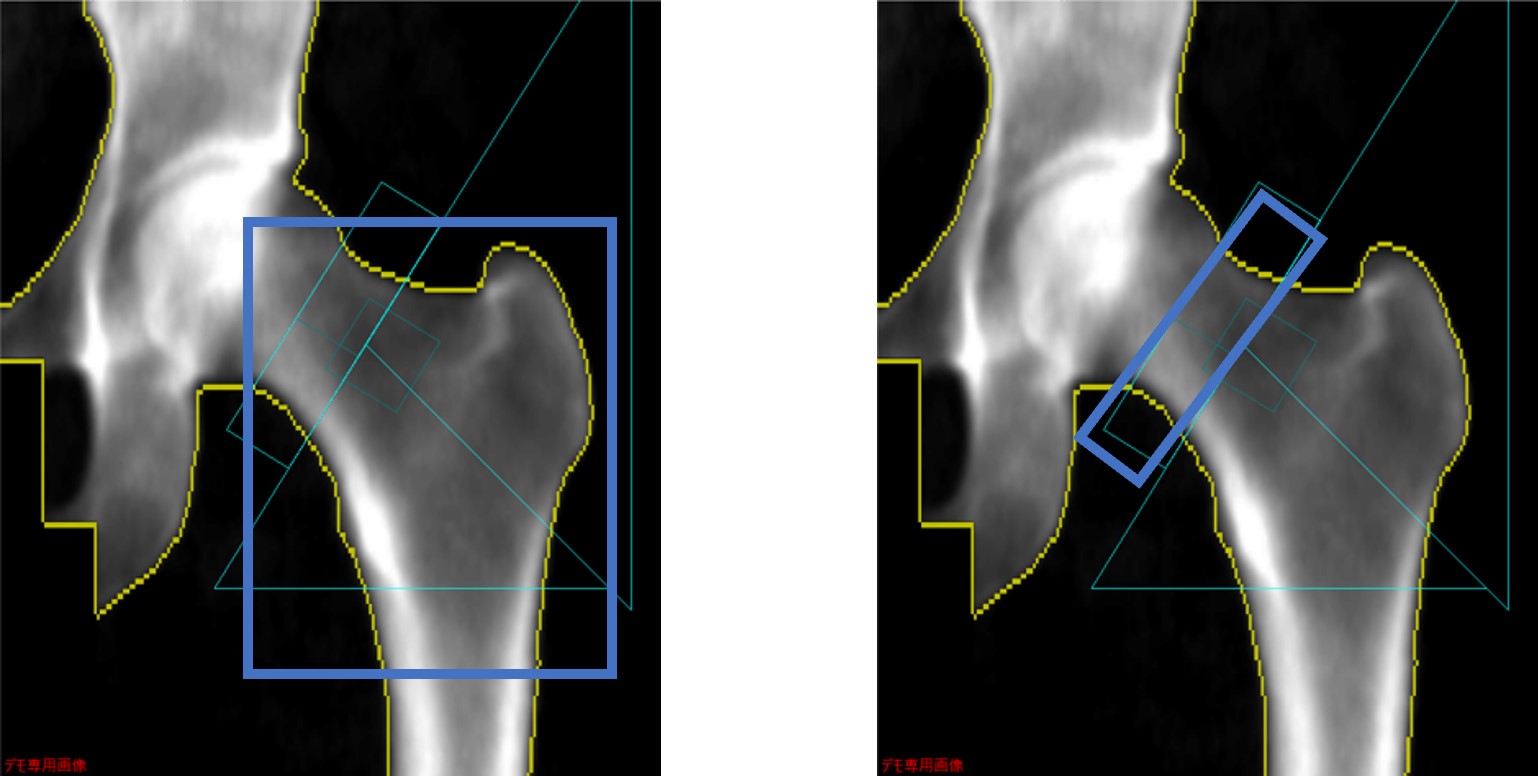

大腿骨解析時は「全大腿骨近位部」と「頚部」を用いる。前述の大腿骨DXAの測定値の適応基準に記載のとおり、全大腿骨近位部と頚部の骨密度のうちYAMに対するパーセンテージが低値の方を採用する。

Clinical Tips_yokohamashitobu10.jpg

全大腿骨近位部(左)と頚部(右)

全大腿骨近位部で評価部位を統一している、という施設も多いかもしれないが、一方でYAM値比較70%以上であっても一方では70%未満、ということもしばしばあり、骨密度の過大評価となる可能性がある。実際に当院が以前大腿骨骨密度を測定した女性患者309例(年齢60-89歳、平均78.2歳)を対象に二部位の骨密度を調査したところ、頚部の方が低値であった症例が53.7%あった4)。そのため、可能な施設は両部位ともに評価することを推奨する。